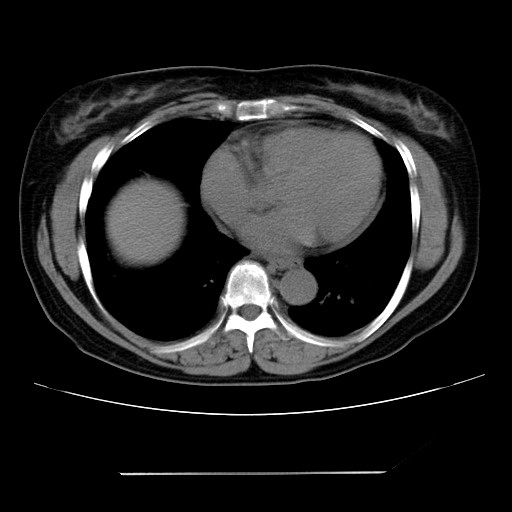

女性,62岁,长期咳嗽,既往从事工作有粉尘接触,有高血压病史,110/150mmhg,近日咳嗽加重,脸面浮肿,请大家帮看下,

1、尘肺;2、慢性支气管炎合并肺部感染;3、心影增大(左房、左室大),考虑高血压性心脏病。

慢支并肺部炎症;右肺结核球?主肺动脉、右肺动脉影不宽,右心室不大,不支持肺心病;无心包积液。

右肺无结核球,是肝上缘